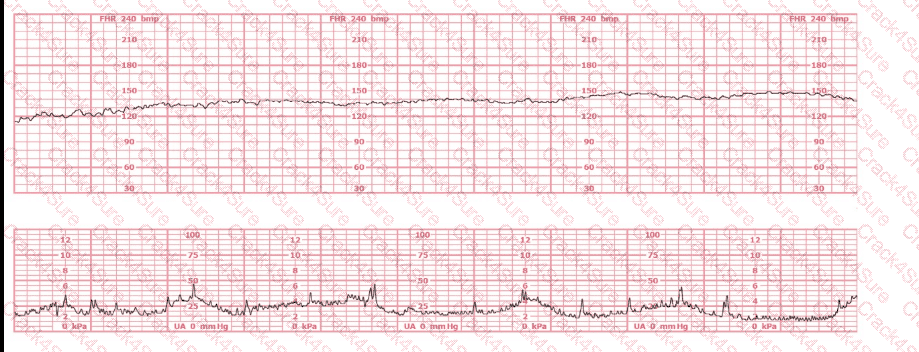

This is a tracing of a multiparous woman in the second stage of labor. The vertex is at +3 station. This pattern has continued for the last 20 minutes. She has been pushing for 2½ hours, and oxytocin is infusing at 12 milliunits/minute. Management should include